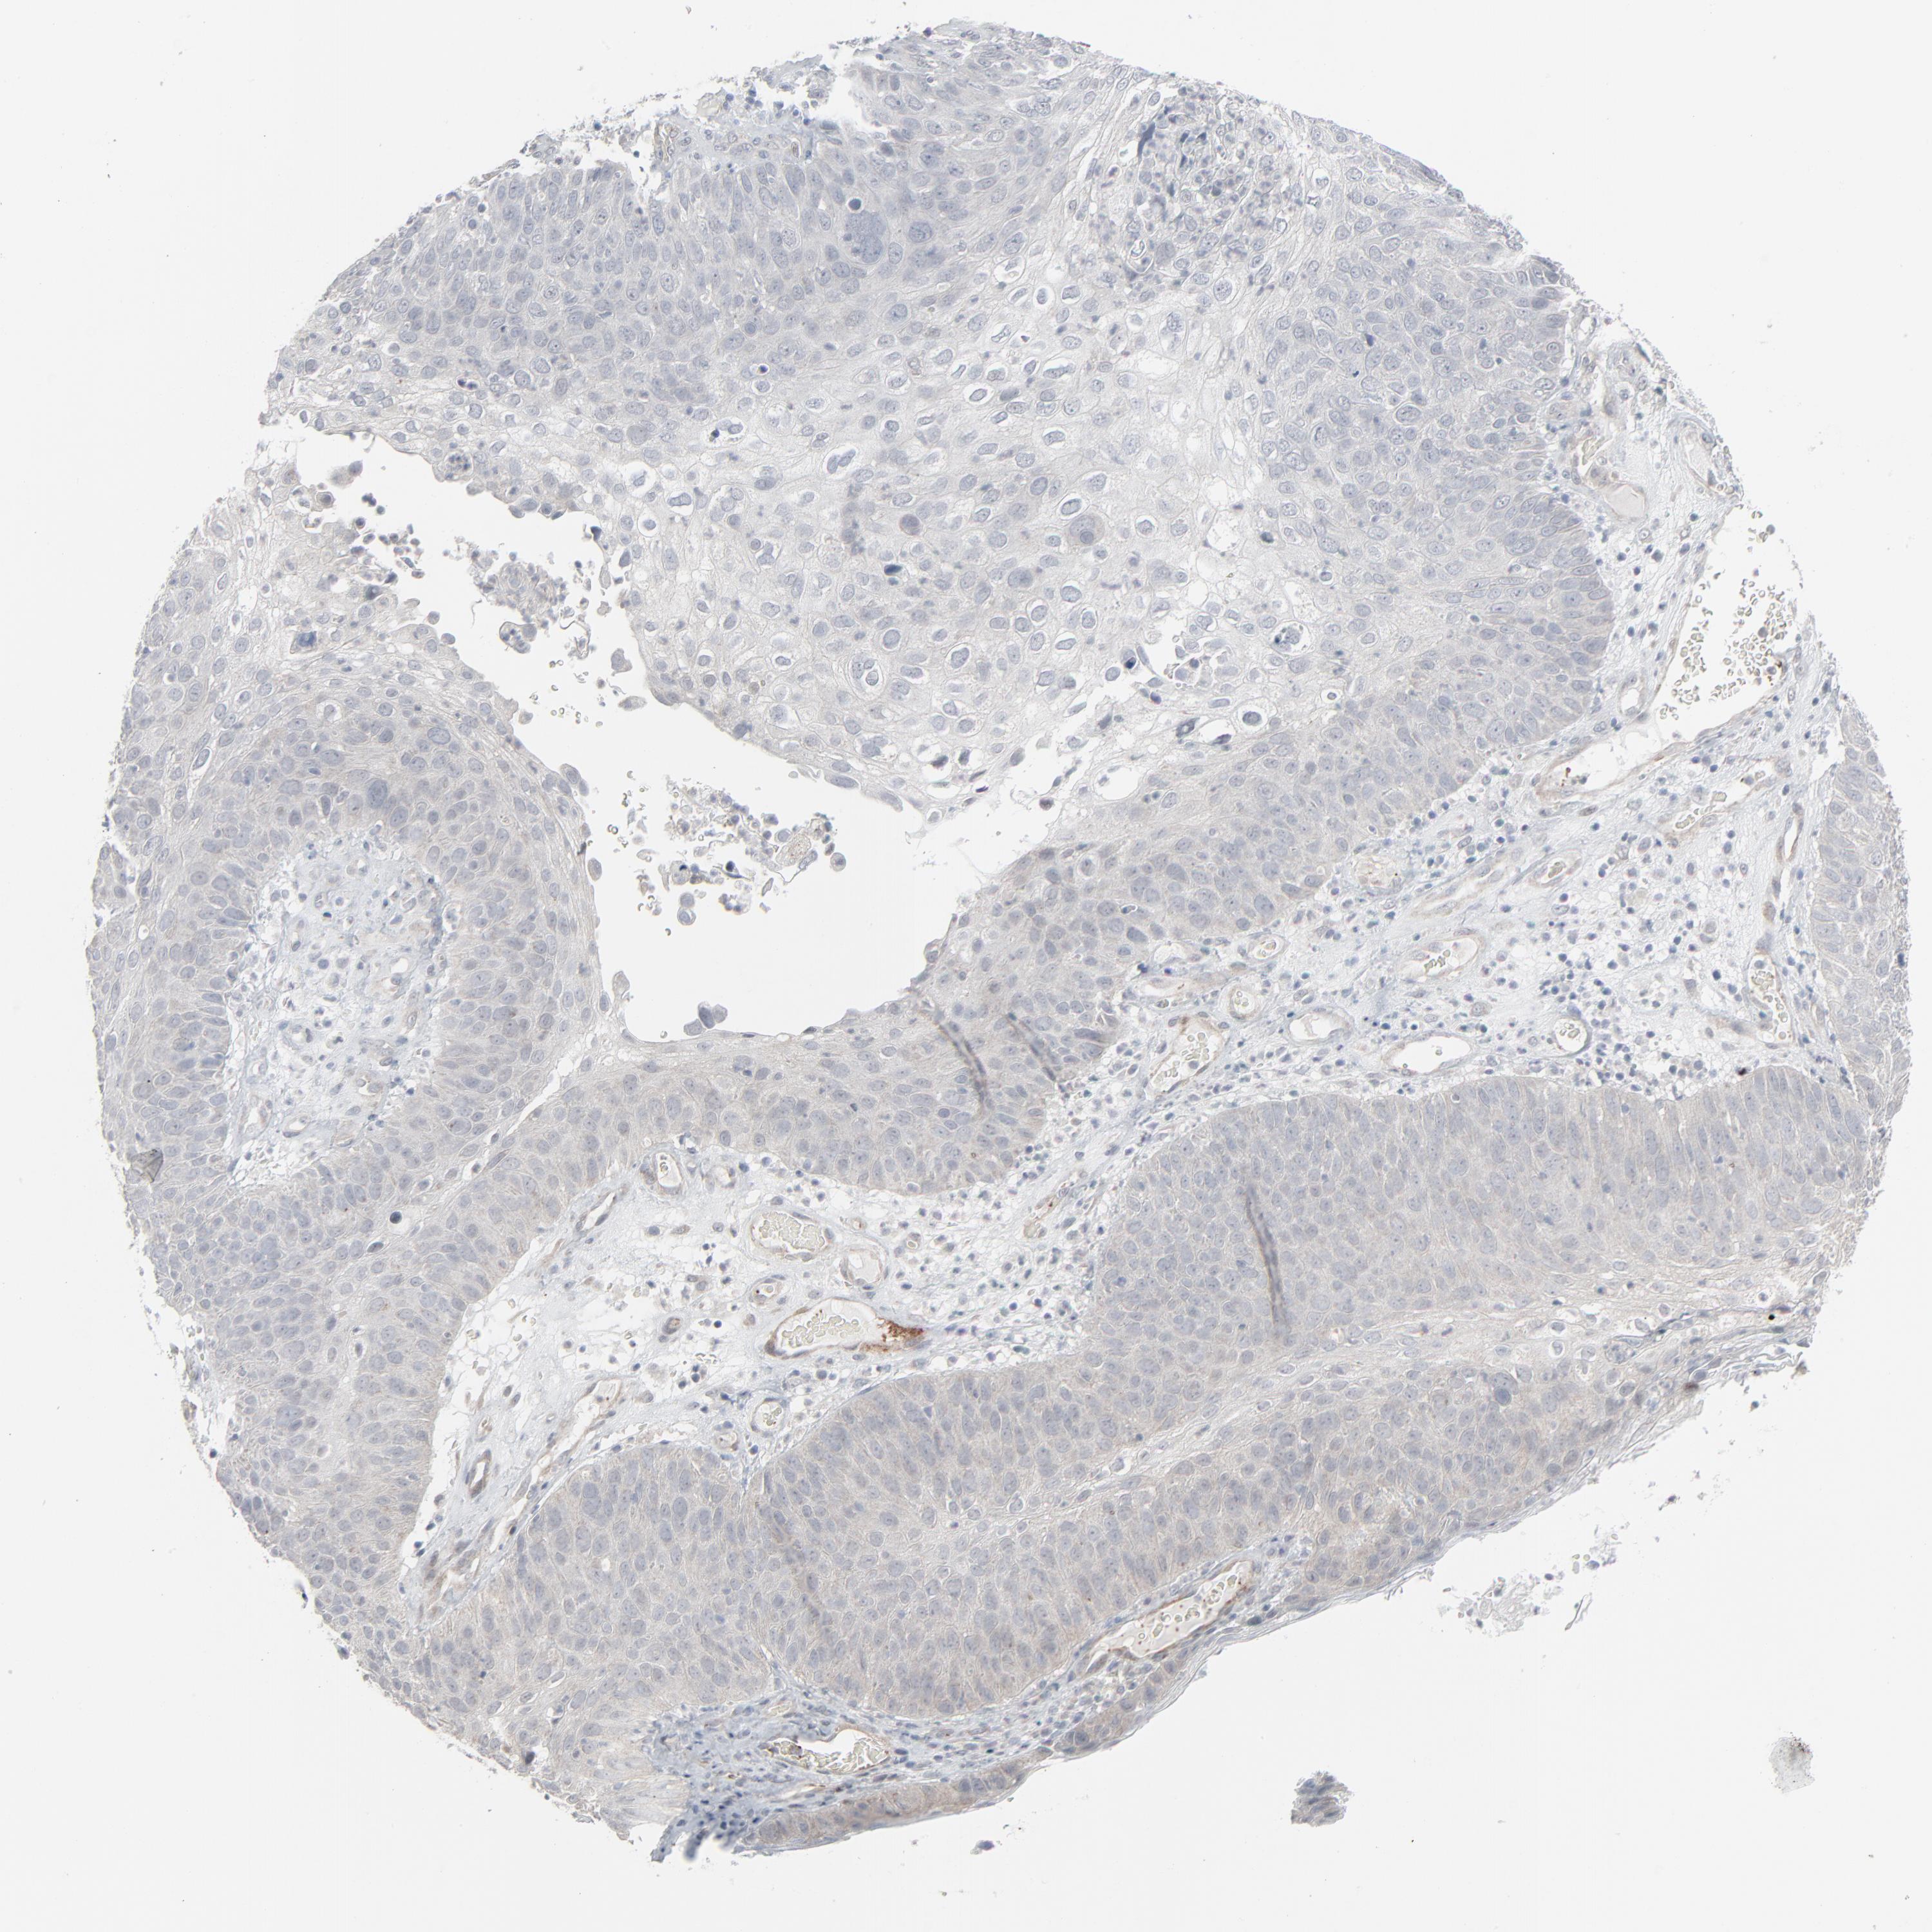

Basal cell and squamous cell cancer

SKIN CANCER - Protein expressioni

A mouse-over function shows sample information and annotation data. Click on an image to view it in a full screen mode. Samples can be filtered based on level of antibody staining by selecting one or several of the following categories: high, medium, low and not detected. The assay and annotation is described here.

Antibody stainingi

Antibody staining in the annotated cell types in the current human tissue is reported as not detected, low, medium, or high, based on conventional immunohistochemistry profiling in selected tissues. This score is based on the combination of the staining intensity and fraction of stained cells.

Each image is clickable and will lead to virtual microscopy that enables deeper exploration of all samples and also displays staining intensity scores, fraction scores and subcellular localization as well as patient and tissue information for each sample.

Antibody HPA003278

Antibody CAB022450

Staining

High

Medium

Low

Not detected

Intensity

Strong

Moderate

Weak

Negative

Quantity

>75%

75%-25%

<25%

None

Location

Nuclear

Cytoplasmic/membranous

Cytoplasmic/membranous,nuclear

Squamous cell carcinoma, NOS